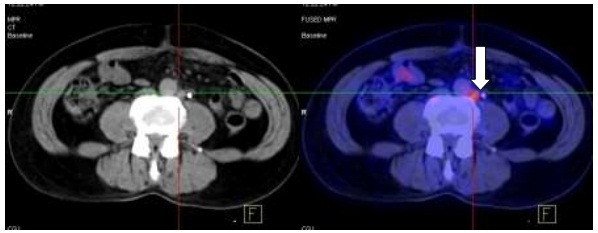

- Chụp PET/CT:

Hình 1.2.Hạch ổ bụng đường kính: 0,6cm, SUV=2,9.

Hình ảnh PET/CT so sánh trước và sau 6 chu kỳ hóa trị:

Hình 2.1. Hình ảnh PET/CT trước điều trị: có khối u đại tràng phải tăng hấp thu FDG.

Hình 2.2. Sau 6 chu kỳ hóa trị: Không thấy hình ảnh khối u đại tràng phải tăng hấp thu FDG.

Hình 2.3. Sau 6 chu kỳ hóa trị: Không thấy hình ảnh hạch ổ bụng tăng hấp thu FDG